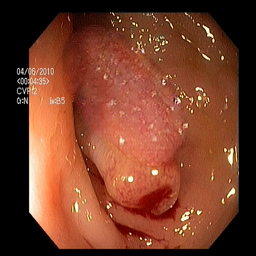

(a) Refer to caption Refer to caption Refer to caption Refer to caption Refer to caption Refer to caption

(b) Refer to caption Refer to caption Refer to caption Refer to caption Refer to caption Refer to caption

(c) Refer to caption Refer to caption Refer to caption Refer to caption Refer to caption Refer to caption

(d) Refer to caption Refer to caption Refer to caption Refer to caption Refer to caption Refer to caption

(e) Refer to caption Refer to caption Refer to caption Refer to caption Refer to caption Refer to caption

(f) Refer to caption Refer to caption Refer to caption Refer to caption Refer to caption Refer to caption

(g) Refer to caption Refer to caption Refer to caption Refer to caption Refer to caption Refer to caption

(h) Refer to caption Refer to caption Refer to caption Refer to caption Refer to caption Refer to caption

Figure 3: Sample data used and generated in the different steps of PolypConnect pipeline. (a) - real polyp images, (b) - manually annotated polyp masks, (c) - randomly selected colon images used as input to the final step of PolypConnect, (d) - extracted edge images of row c. (e) - extracted edge images of polyp regions of row a using the masks of row b. (f) - combined edge images of row d and f. (g) - generated polyp on the images of row c using EdgeConnect. (h) - generated samples from AOTGAN.